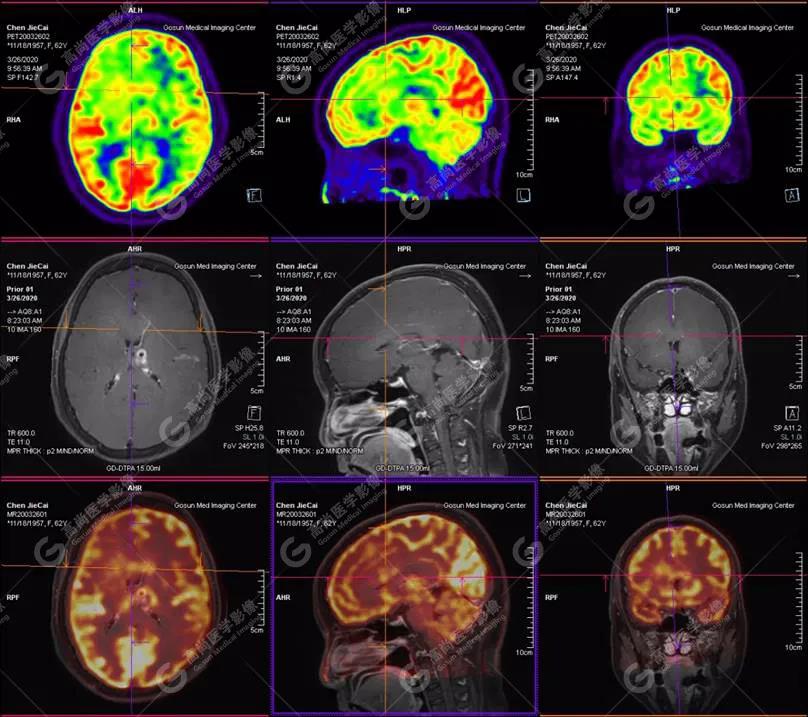

【廣東高尚醫(yī)學影像】多模態(tài)影像|顱內(nèi)淋巴瘤PET-MR融合顯像1例

失眠伴記憶力減退近一月入院檢查,無頭痛、嘔吐、四肢活動正常

外院CT提示,顱內(nèi)多發(fā)占位,轉(zhuǎn)移瘤可能

左側(cè)顳葉、頂葉、左側(cè)基底節(jié)區(qū)及胼胝體部多發(fā)結(jié)節(jié)狀高代謝病灶,部分合并囊變、出血,MR平掃+增強示不均勻輕、中度強化,綜合考慮為顱內(nèi)原發(fā)惡性腫瘤,以淋巴瘤可能性大

彌漫大B細胞淋巴瘤

淋巴瘤病變多位于中線兩旁的深部腦實質(zhì)、側(cè)腦室周圍及腦表面,甚少累及腦膜和顱骨,幕上多于幕下,呈分葉狀或握拳狀,水腫及占位效應較輕,部分病灶內(nèi)可見囊變、出血及其邊緣的硬環(huán)征、尖角征、臍凹征,增強掃描呈現(xiàn)的“臍凹征或者“握拳征”是淋巴瘤較為特征性的一個表現(xiàn)。

18F-FDG PET PET顯像中呈明顯高代謝病灶。

顱內(nèi)惡性淋巴瘤對18F-FDG的攝取率很高,一般SUV在5~10以上,18F-FDG PET顯像中攝取明顯高于正常腦皮層,因此具有特征性。